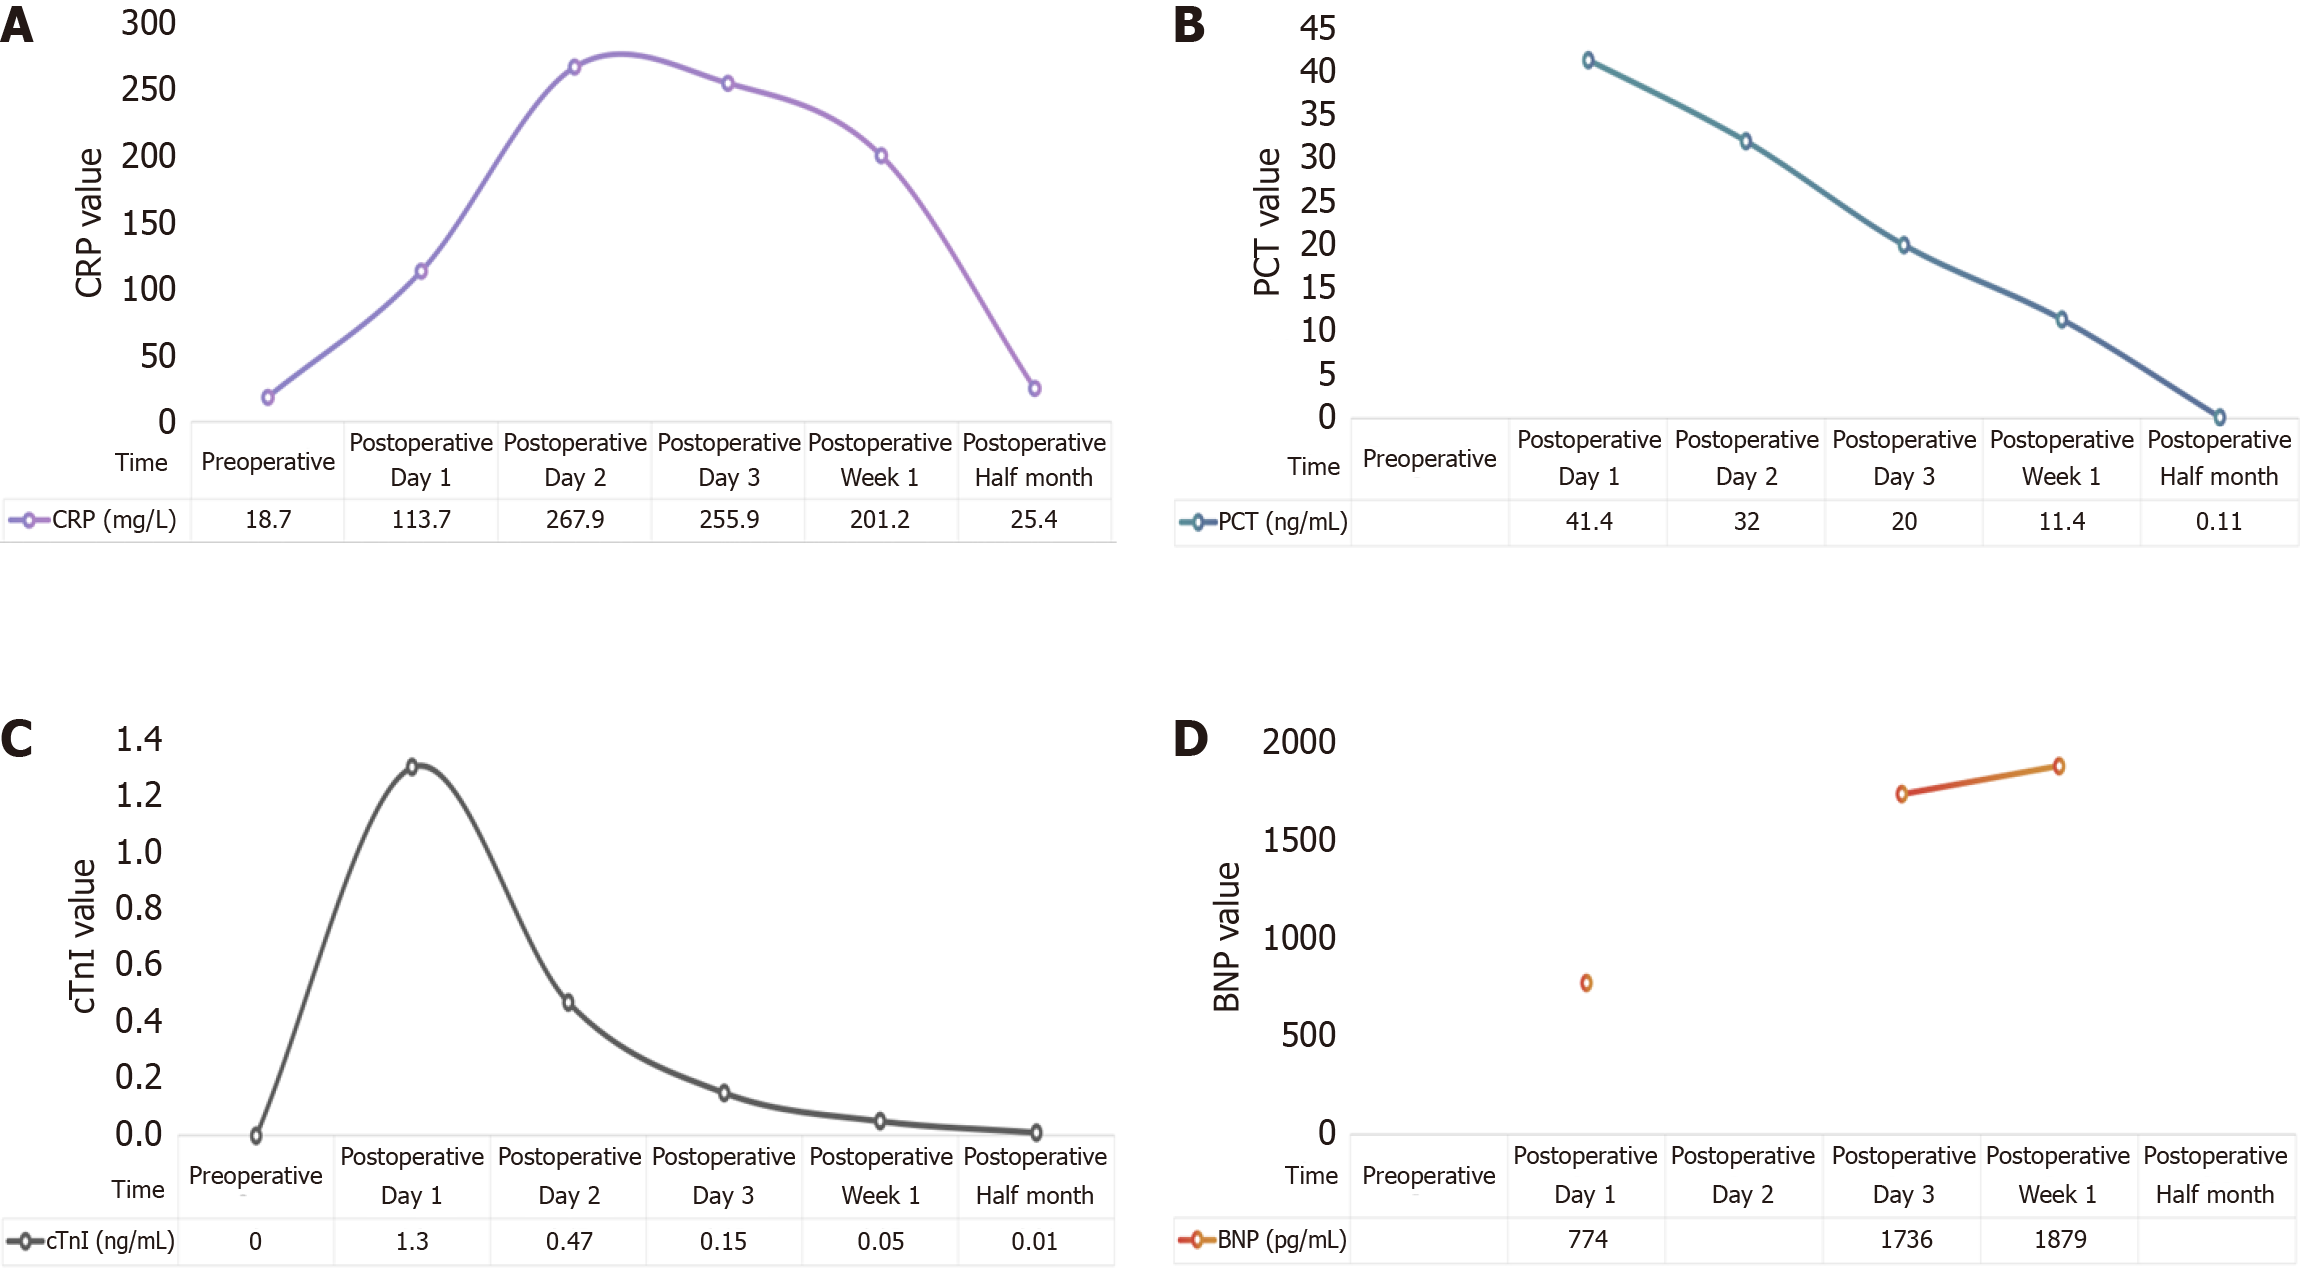

Postoperative pathology (Figure 2) confirmed tumor invasion through the entire intestinal wall and into the pancreas, with neural invasion (+). Immunohistochemical analysis demonstrated positive staining for squamous differentiation markers [P40, cytokeratin (CK) 5/6, P63] with strong pan-CK expression, along with CK7 positivity, while showing negativity for intestinal differentiation markers (CK20, caudal-type homeobox protein 2, villin) and somatostatin receptor 2. This immunoprofile supports the diagnosis of SCC and argues against a colorectal adenocarcinoma origin or neuroendocrine differentiation, with additional findings including a moderate proliferative index (Ki67 approximately 20%) and preserved vascular (CD34+) and lymphatic (D2-40+) architecture. Within 24 hours postoperatively, the patient developed agitation with elevated CRP and cardiac troponin I levels (Figure 3). Electrocardiography demonstrated acute non-ST-segment elevation myocardial infarction, attributed to perioperative ischemic hypoperfusion exacerbated by concurrent intra-abdominal infection. Empirical antimicrobial therapy with ceftriaxone was initiated alongside continuous negative-pressure peritoneal irrigation. Adjunctive therapies included antiplatelet therapy (aspirin), lipid-lowering therapy (atorvastatin calcium), and coronary vasodilation (tanshinone). Nutritional Risk Screening (2002) revealed a score of 6 points, prompting intravenous administration of glucose, amino acids, vitamins, and fat emulsion. On postoperative day 5, purulent drainage fluid cultured multidrug-resistant Escherichia coli, while Doppler ultrasonography of the lower extremities revealed bilateral calf dorsal muscular venous thrombosis. Antimicrobial therapy was escalated to ertapenem based on antimicrobial susceptibility testing, with concurrent initiation of low-molecular-weight heparin anticoagulation. Amylase-negative abdominal fluid analysis excluded pancreatic leakage. Following comprehensive therapeutic inter